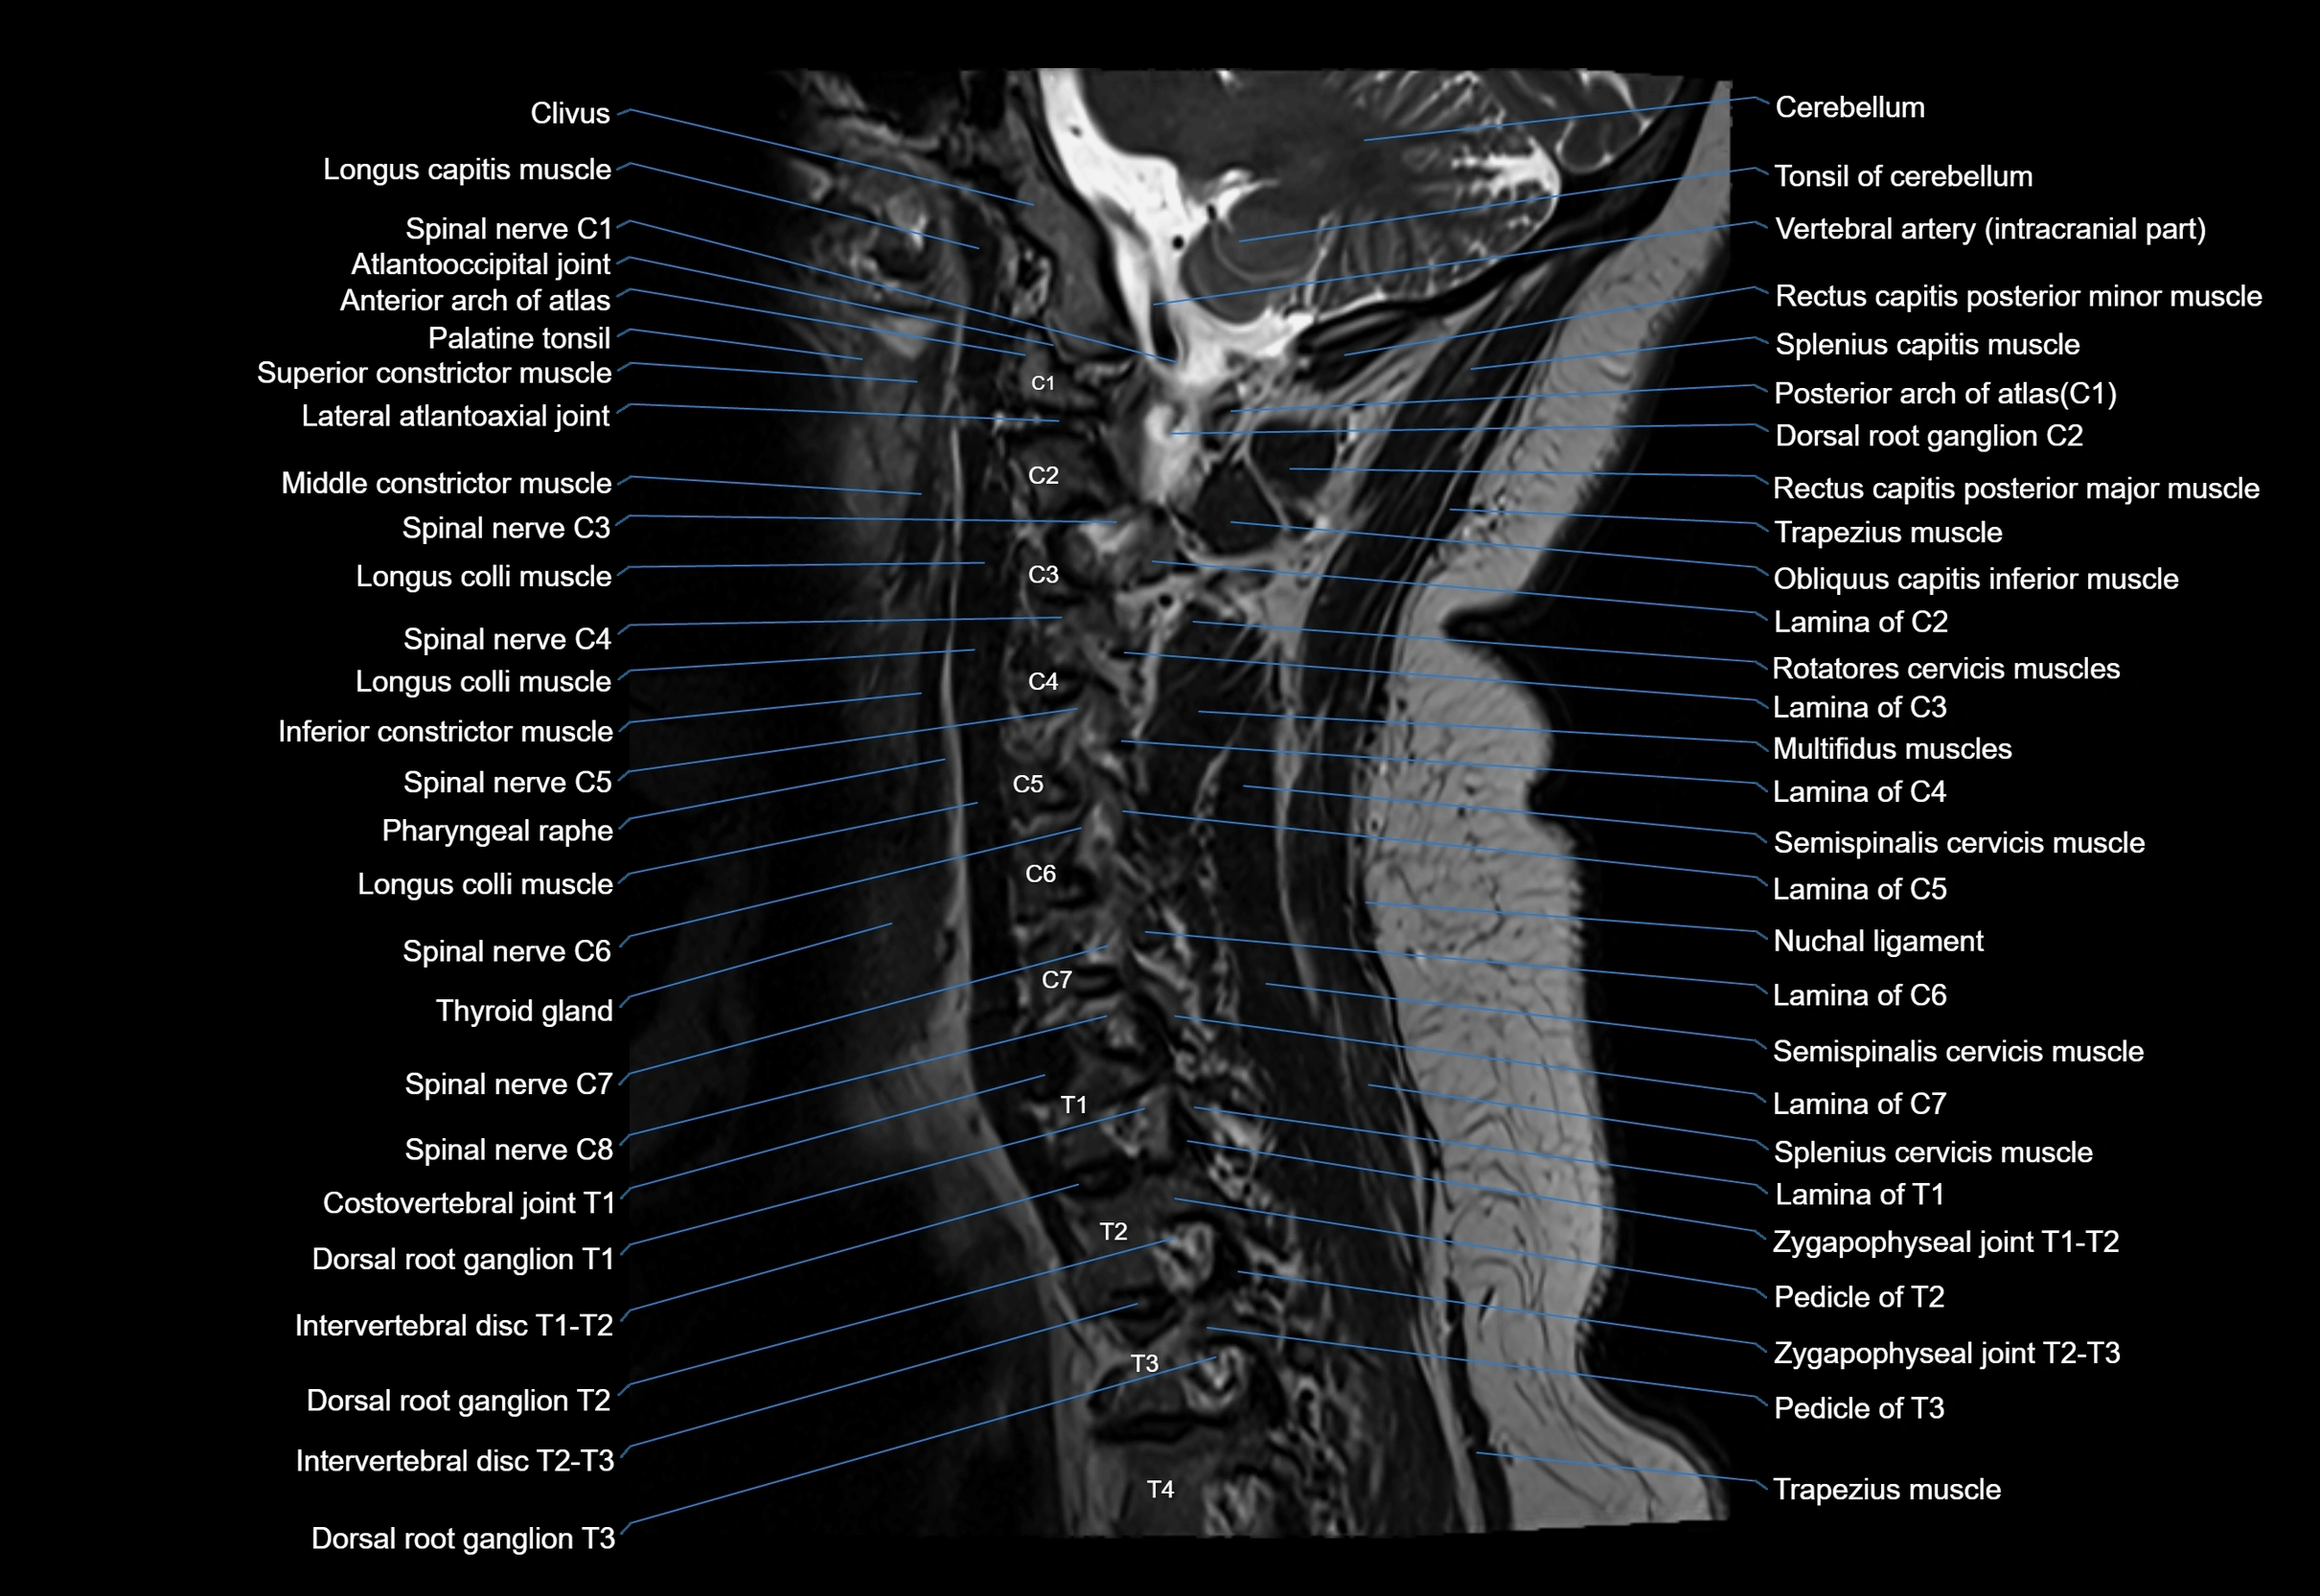

MRI image

image